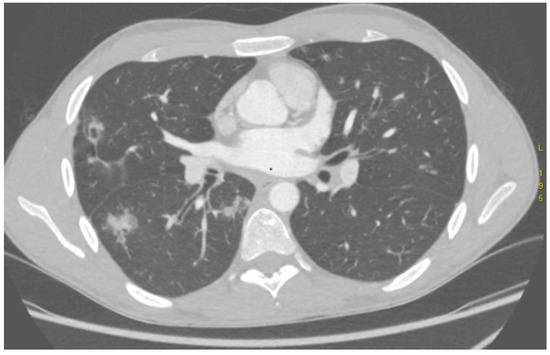

The Role of Preprocedural Computed Tomography Angiography in Enhancing Arterial Embolisation for Life-Threatening Haemoptysis: A Case Series

Haemoptysis arises from diverse respiratory diseases and may involve a broad spectrum of thoracic vessels. Arterial embolisation (AE) is an effective, repeatable, minimally invasive treatment option for life-threatening haemoptysis. This case series included 10 patients (mean age 34 years; six males; five with cystic fibrosis) who underwent 17 AE procedures for life-threatening haemoptysis between January 2018 and September 2025. The study assessed the role of wide-field computed tomography angiography (CTA), extending from the thoracic inlet to L2, in preprocedural planning, bleeding localisation and detection of systemic collaterals. CTA accurately predicted the culprit region in 16 out of 17 procedures. Non-bronchial systemic arteries were identified in 6 out of 10 patients, consistent with previous reports. CTA showed strong concordance with angiography and enabled the detection of uncommon collaterals, including subclavian and phrenic branches. Recurrence of hemoptysis occurred in one patient during follow-up; however, three patients were lost to follow-up. Wide-field CTA enhances the identification of systemic feeders and supports procedural planning, potentially reducing recurrence associated with missed culprit vessels. AE remains a valuable option for haemoptysis control in cystic fibrosis, with outcomes further improved following initiation of CFTR modulators. The small sample size and incomplete follow-up limit generalisability, but findings highlight the importance of CTA in guiding AE and improving clinical outcomes. Full article

Show Figures

Figure 1